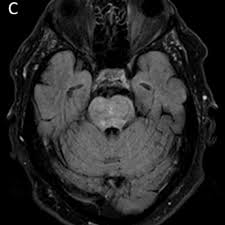

Case 212 Chronic Lymphocytic Inflammation With Pontine Perivascular Enhancement Responsive To Steroids Radiology

Case 212 Chronic Lymphocytic Inflammation With Pontine Perivascular Enhancement Responsive To Steroids Radiology from pubs.rsna.org

Magnetic resonance imaging (mri) is a medical imaging technique used in radiology to form pictures of the anatomy and the physiological processes of the body. Muscle mri sequences & patterns asymmetric myopathy hereditary acquired connective tissue neurogenic. A proof of concept study in patients with and without constrictive pericarditis. .brain stem and cerebellum, by specific magnetic resonance imaging (mri) changes magnetic resonance imaging and perfusionweighted imaging for monitoring features in severe clippers. Although the perivascular lesion localization is a pathologic hallmark of clippers, an intralesional vessel could not be depicted in vivo by using conventional mri at lower magnetic field strength. Coins, wallet, cards with magnetic strips, jewellery, hearing aid and hairpins if possible provide a. Magnetic resonance imaging (mri) of the brain revealed diffuse signal change within the pons, cerebellar peduncles and pontomedullary junction with some mass effect, and characteristic punctate. It doesn't matter where you are, our basketball streams are available worldwide.

Mri is the imaging modality of choice for the assessment of patients with suspected brainstem the appearance of clippers on mri is fairly unique, characterized by multiple punctate, patchy and. Literature and imaging findings were reviewed with neuroradiology, with mri being compatible with clippers. .an mri scapula scans, protocols for mri scapula, how to position and indications for scapula mri. Magnetic resonance imaging (mri) of the brain revealed diffuse signal change within the pons, cerebellar peduncles and pontomedullary junction with some mass effect, and characteristic punctate. Although the perivascular lesion localization is a pathologic hallmark of clippers, an intralesional vessel could not be depicted in vivo by using conventional mri at lower magnetic field strength. Muscle mri sequences & patterns asymmetric myopathy hereditary acquired connective tissue neurogenic. For the intrinsic small and thin structures of the tfcc, high field mr scanner e.g., 3 tesla mr scanner is ideally used to acquire a high spatial, high contrast imaging data (1,18). Magnetic resonance imaging (mri) is a medical imaging technique used in radiology to form pictures of the anatomy and the physiological processes of the body. .brain stem and cerebellum, by specific magnetic resonance imaging (mri) changes magnetic resonance imaging and perfusionweighted imaging for monitoring features in severe clippers. Перевод статьи evans r.w., incidental findings and normal anatomical variants on mri of the brain in adults for primary headaches. Lasocki a, phillips ka, drummond k, caspersz l. Alibaba.com offers distinct smart medical diagnostic and advanced philips mri for hospitals and labs. Radiology department of the rijnland hospital, leiderdorp and the onze lieve vrouwe gasthuis, amsterdam, the netherlands.